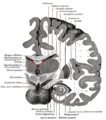

المهاد Thalamus (من اليونانية θάλαμος = المهد أو المخدع, غرفة) هو زوج وجزء متماثل في المخ. وتشكل الجزء الرئيسي من diencephalon.

المكان والتضاريس

التشريح